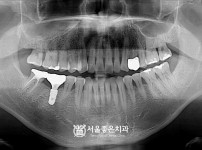

|  | 341 |  | 뼈이식 수면 임플란트 5개 - 네오 임플란트 / 심하게 흔들리는 치아 발치 후 임플란트